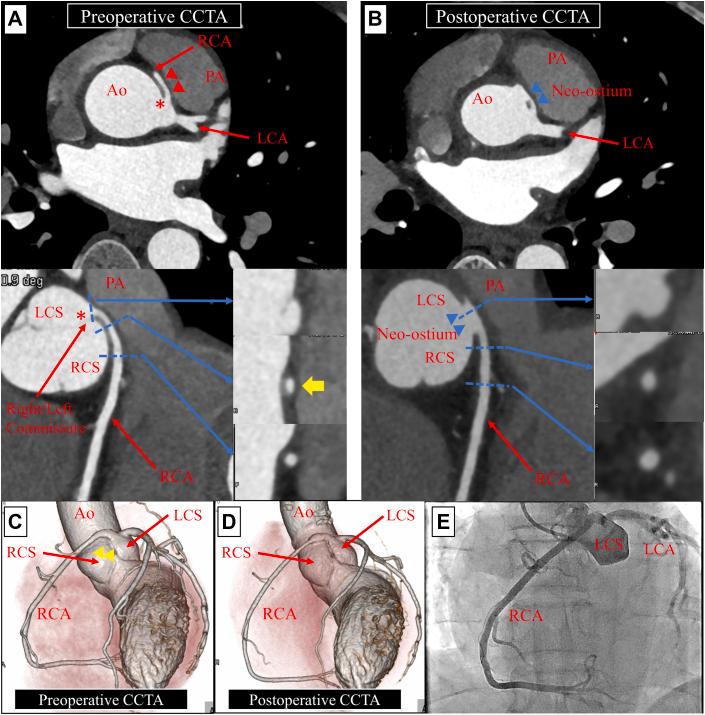

外科修复冠状动脉异常中的定量心肌灌注

Quantitative Myocardial Perfusion in Surgically Repaired Coronary Artery Anomaly.

The anomalous aortic origin of the right coronary artery with an intramural course is rare and can cause myocardial ischemia, for which surgical repair is indicated. We present the case of a 49-year-old man with this anomaly whose preoperative myocardial perfusion positron emission tomography revealed inducible ischemia. Comparison of the preoperative and follow-up (6 months) positron emission tomography findings showed significant improvement in regional myocardial flow reserve and relative flow reserve, in keeping with the improvement in symptoms. However, positron emission tomography/myocardial perfusion imaging findings were difficult to interpret.

摘要

右冠状动脉发自主动脉异常且走行于壁内的情况较为罕见,可导致心肌缺血,对此需行手术修复。我们报告了1例患有这种异常的49岁男性病例,其术前心肌灌注正电子发射断层扫描显示有诱发性缺血。术前和随访(6个月)正电子发射断层扫描结果比较显示,局部心肌血流储备和相对血流储备有显著改善,与症状改善相符。然而,正电子发射断层扫描/心肌灌注成像结果难以解读。